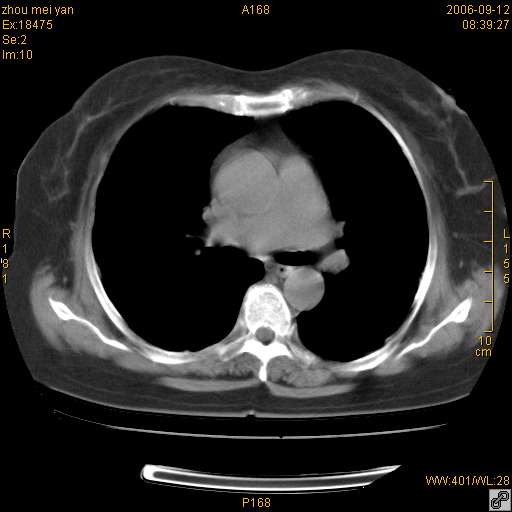

患者、女、55岁。因心率失常住院检查ct发现胸部多发结节。腹部b超肝、胆、胰、脾、肾、子宫附件未见异常。无结核病史,无粉尘接触史。请大家来会诊。谢谢!

病变位于胸膜,多发结节,边界清楚,内见小结节状钙化。其它未见异常。

双侧胸膜多发结节,形态不规则,边缘较清楚,每一个结节中心似乎都有钙化点的特征,与胸膜广基相切。临床无结核病史,无粉尘接触史。

胸膜间皮瘤可能性大。在气管隆突前可见一肿大淋巴结影。

影像表现十分有特点:双侧肋胸膜及膈胸膜广泛散在分布大小在2至6mm左右,较大病灶中心可见钙化。

考虑:1、胸膜间皮瘤?2 类风湿性胸膜结节?

考虑恶性胸膜间皮瘤可能性大,病灶位于胸膜,以宽基地与胸膜相连,呈结节样改变,部分病灶内可见点状钙化影。请各位老师多多指导!